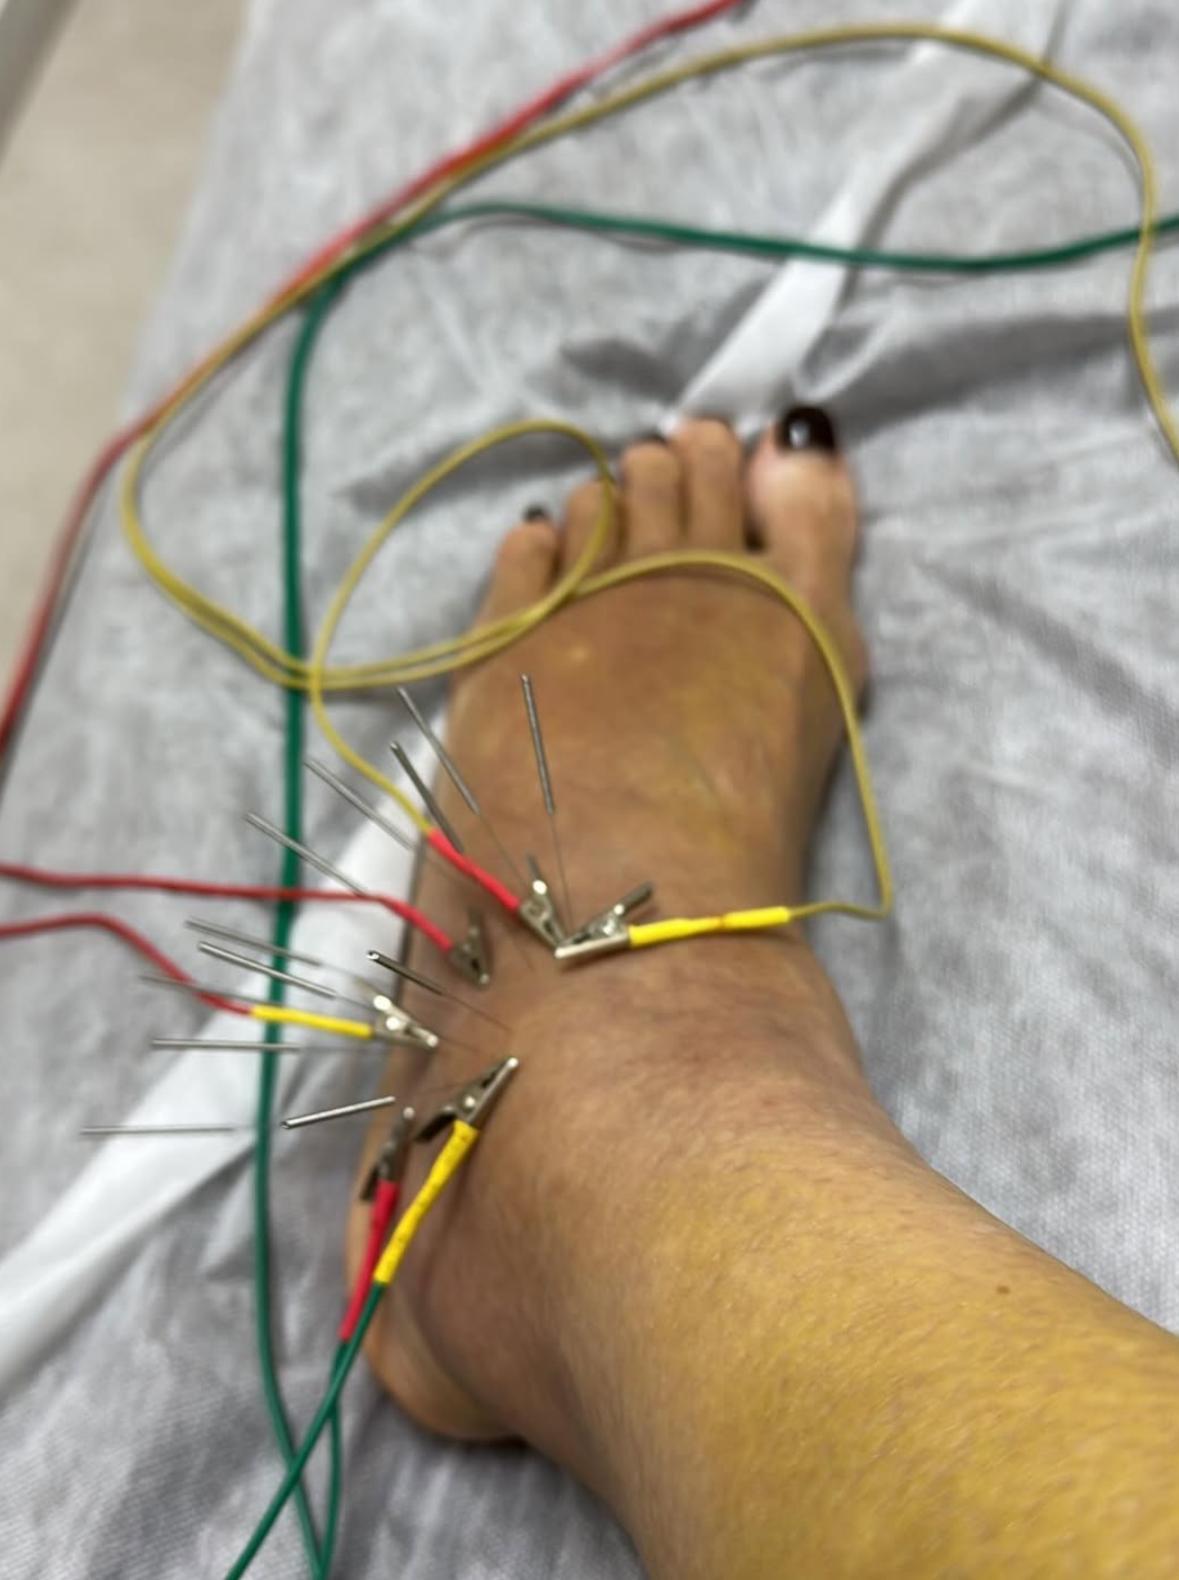

余安安在上年播出的劇集《家族榮耀之繼承者》演戴綺婷一角,獲得觀眾大讚演技出色,最近她甚少參與幕前演出。余安安前日(8日)在社交網自爆兩星期前人生第一次拗柴,後來情況嚴重到骨裂,需要接受中西合璧治療。另外她還上載一系列腳傷情況的照片,她需要靠雙手撐住枴杖行路,而左腳要用護具固定。

余安安發文指拗柴原本以為拗柴的情況並不是太嚴重,所以當晚忍痛陪伴孫仔去看燈飾。她續說:「再過多兩日又覺得唔多妥去照埋X-Ray,原來骨裂咗,不幸中之大幸係冇移位,要買對超貴嘅boot着,慶幸係左腳,右腳最近仲可以揸到車。」